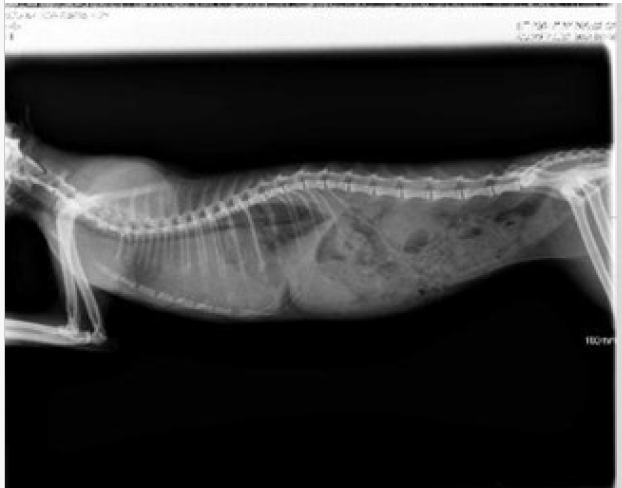

En esta segunda parte, analizaremos en profundidad el tratamiento con GS-441524, revisando sus beneficios, posibles problemas y cómo identificar si está siendo efectivo.